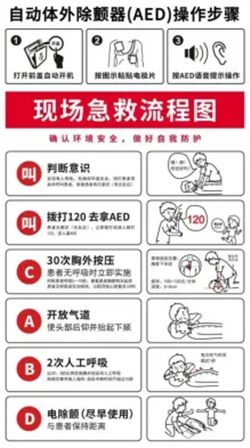

四、黄金4分钟:如何正确施救?

心源性猝死的抢救成功率与时间呈指数级下降:4分钟内实施心肺复苏(CPR)+ 自动体外除颤器(AED)除颤,生存率可达50%-70%。10分钟后 再施救,生存率几乎为0。

急救四步法

判断意识: 轻拍双肩、大声呼喊,同时观察胸廓起伏、检查颈动脉搏动(非专业人士可不查脉搏,直接观察呼吸)。

胸外按压: 位置——两乳头连线中点(或胸骨中下1/3处);深度——5-6厘米;频率——100-120次/分钟。

开放气道: 仰头抬颏法,清除口腔异物。

人工呼吸: 每30次按压后给予2次吹气(每次吹气约1秒,见胸廓隆起)。

尽早除颤: 如现场有AED,立即按语音提示操作,无需担心误用。